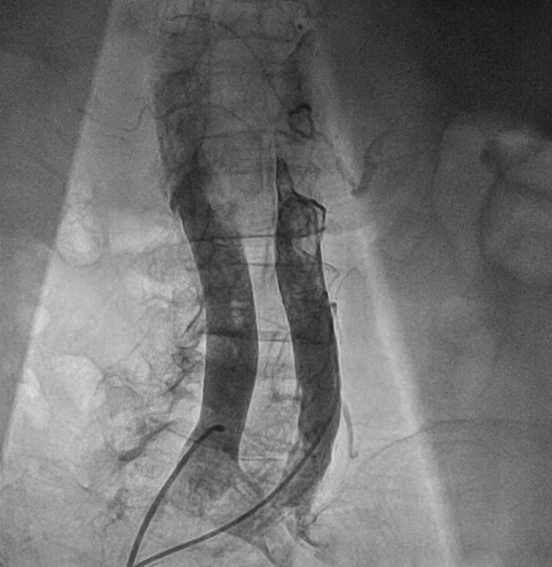

完成瓣膜置入后撤出22F输送鞘并用封堵器封堵腹主动脉与下腔静脉间的动静脉瘘,封堵器完全释放后腹主动脉及下腔静脉内造影均显示封堵效果良好,未见明显造影剂外渗。

封堵器释放后腹主动脉造影

封堵器释放后下腔静脉造影